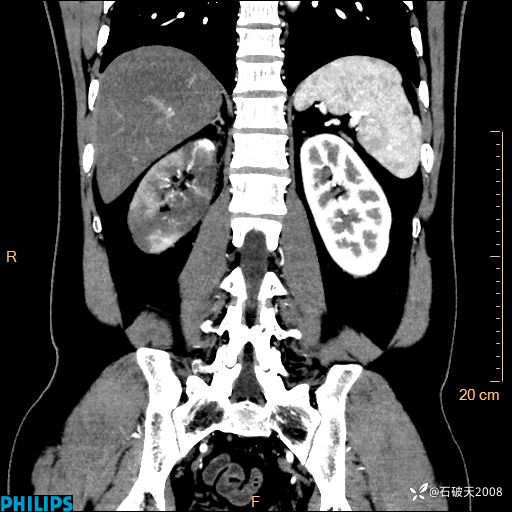

这个病例诠释了“腹部不增强,等于耍流氓”

男 44岁 主 诉:右侧腰背部疼痛4天。

现病史:4天前无明显诱因出现右侧腰背部疼痛,呈阵发性发作,疼痛性质描述不详,无尿频、尿急、尿痛,无恶心呕吐、腹泻、黑便,无胸闷、胸痛、呼吸困难,无发热、寒颤等,休息后缓解不明显,昨日到我院门诊就诊,行泌尿系彩超示:1.双肾肾砂;2.前列腺体积稍大。予“肾石通丸”、“左氧氟沙星片”等药物口服治疗后无缓解,昨日夜间再次到我院就诊,急诊科予“复方双氯芬酸钠注射液”肌注处理后好转,今晨仍感右侧腰背部疼痛,再次来诊并由门诊以“腰痛”为初步诊断收入我科。发病来患者神志清,精神稍差,饮食睡眠欠佳,小便正常,大便不畅,体重近期无下降。

MIP